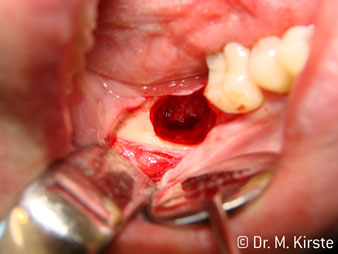

Die professionelle Lagergestaltung im Innenleben des Handstückkopfes garantiert einen ruhigen Lauf der Bohrer, bei der Zahn- oder Wurzelseparation (Abb. 4 - 9) zeigt sich ein beeindruckendes Schnittbild ohne Schlageffekte.

Abb. 5

Abb. 4